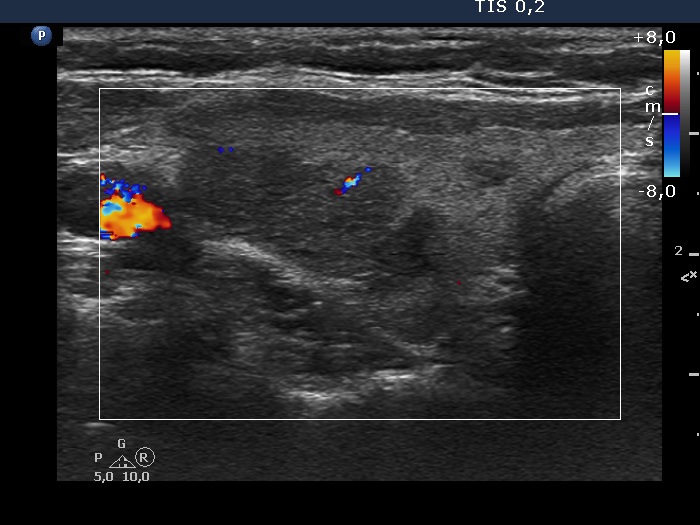

First examination (first, third and fifth rows of images):

Ultrasonography. The thyroid was echonormal and contained multiple inhomogeneous, partly blurred hypoechogenic and moderately hypoechogenic discrete lesions. Multiple lymph nodes were found on both sides of the neck.